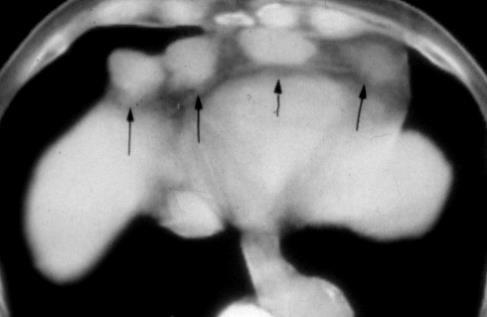

Nódulos pulmonares múltiples. (flechas verdes). Masas paratraqueales. (flechas amarillas). Dudoso ensanchamiento retrocrural (flechas negras). sigue….

Ttawfik A et al. Trans-diaphragmatic Pathologies: Anatomical Background and Spread of Disease on cross-sectional Imaging. Current Problems in Diagnostic Radiology. 2021.

T. mixto de células germinales del testículo

izquierdo Metástasis pulmonares. (flechas verdes). Ganglios paratraqueales. (flechas amarillas). Ganglios retroperitoneales (flechas negras)

Tawfik A et al. Trans-diaphragmatic Pathologies: Anatomical Background and Spread of Disease on cross-sectional Imaging. Current Problems in Diagnostic Radiology. 2021.